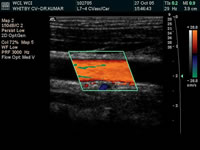

Carotid and Vertebral Doppler:

The Carotid Doppler is an ultrasound done on the

carotid arteries of the neck. This test is done to

check the blood flow of the arteries to observe if

there are any flow restrictions on either side.

Patients may have this test if they have had a previous

stroke. Other symptoms are dizziness, transient stroke,

or loss of vision. It can also be done on asymptomatic

patients pre/post operation, or with high risk factors.

The total time involved is 45 minutes to an hour.